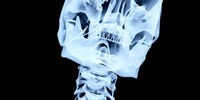

Fluoroscopy or CT scan may be used to identify where the needle should be placed. This is recommended to make sure that it is delivered in the right place and patients receive the top benefits. The procedure is just one of the things used for pain treatment, other such options: surgery, oral medications, physical therapy.

After the area is numb, physicians may use the imagine devices to figure out where to place the shot. Contrast material is then injected into the area so the doctor can guarantee the correct distribution of medication. The epidural shot is slowly delivered. Patients may feel nothing, or some slight tingling or pressure, during this process.